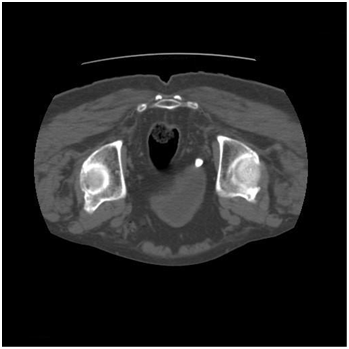

A 70year male presented to us with complaints of dysuria. There was no history of flank pain. He was a known asthmatic and had undergone transurethral resection of prostate 7years back. Physical examination was unremarkable. Urinalysis showed >100 pus cells per high power field. Urine was sent for culture. Routine biochemical parameters were normal. Ultrasonography showed a calculus at the right ureterovesical junction. An unenhanced helical CT scan was done which showed a right ureterovesical calculus of size 10mm and density 450HU (Figure 1). There was no hydronephrosis, hydroureter, perinephric or periureteral stranding. The CT was repeated in the prone position to differentiate whether it was calculus at the ureterovesical junction or if it was calculus in the bladder lying near the ureterovesical junction. The prone scan showed no change in the position of the calculus (Figure 2), which led to the conclusion that it was an ureterovesical junction calculus. Ureterorenoscopy was planned. However, on cystoscopy it was found that the calculus was not at the ureterovesical junction but was in a paraureteral diverticulum having a narrow mouth. It was dealt with by fragmentation using pneumatic lithotripsy and then removing the fragments.

Figure 2 Unenhanced Helical CT Scan in Prone position.

Unenhanced Helical CT Scan is now an established modality to evaluate patients with renal colic. When a calculus is seen near the ureterovesical junction it is important to determine whether it is impacted at the ureterovesical junction or if it has already passed in the bladder and is lying near the ureterovesical junction. Clinical signs and symptoms cannot accurately differentiate between them.4 Ureteral dilatation and perinephric stranding are also not useful signs in differentiating between them. CT scan done in prone position helps to differentiate these two conditions. Calculus that does not change position is impacted at the ureterovesical junction while calculus which falls dependently in the prone position is in the bladder.3 We had done a prone scan in our case to differentiate between the two. As there was no change in the position of the calculus, a diagnosis of calculus at the ureterovesical junction was made. On cystoscopy we found the calculus to be in a paraureteral diverticulum which had a narrow opening. This explained the findings of the prone CT scan. As the mouth of the diverticulum was narrow the calculus could not fall in a dependent position and the lack of change of position made us to diagnose it as being present at the ureterovesical junction.